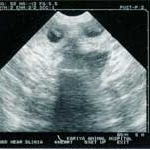

birth3.jpg<2002.02.05>赤ちゃんが出来た! エコー検査で2〜3頭いるようです。

birth3_1.jpg<2002.03.02>食欲旺盛、妊婦体型なのに太らない。なんと6匹もお腹にいるのが判明!